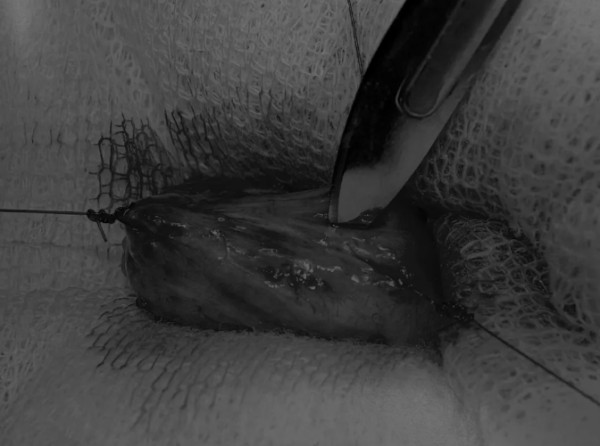

在牵引缝线之间选择血管扩张较差的区域用手术刀切开膀胱壁(图3)。在牵引缝合线之间用手术刀在血管不良的区域做切口。切开膀胱壁后,膀胱内的手术可按手术方案实施,例如取出结石(图4)。

图4 这张图显示了从膀胱中取出的大量结石